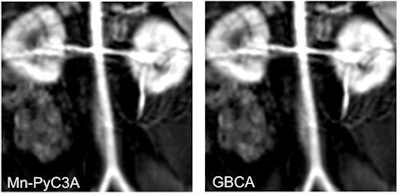

Contrast-enhanced MR image of the abdominal aorta, renal arteries, and kidneys of a baboon acquired with the manganese-based agent Mn-PyC3A (left), compared with the same scan with a gadolinium-based contrast agent (right). Images courtesy of Eric Gale, PhD.Gadolinium, on the other hand, is not naturally found in the human body, and recent studies have raised questions about whether there are long-term adverse effects due to the metal's retention in the brain and other tissue years after a GBCA-enhanced MRI scan.

In the current study, the researchers compared Mn-PyC3A with a commonly used GBCA in a baboon model. Each animal underwent two MRI scans under identical conditions -- one with Mn-PyC3A and one with the GBCA. The dosages and imaging protocols were the same as those used for human patients.